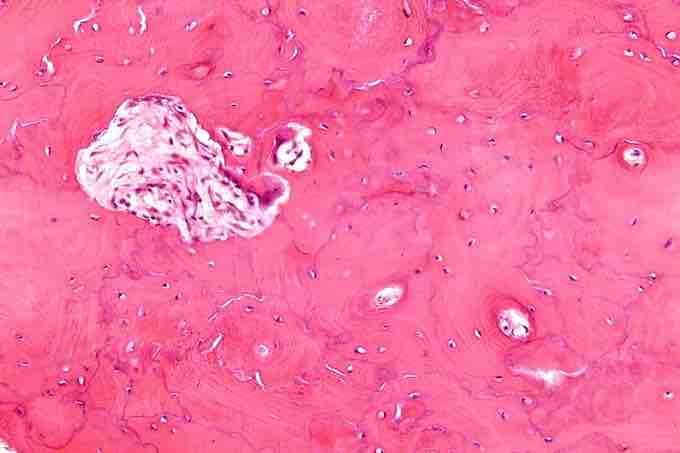

Initially, in Paget's disease there is a marked increase in the rate of bone resorption at localized areas caused by large and numerous osteoclasts. These localized areas of osteolysis are seen radiologically as an advancing lytic wedge in long bones or osteoporosis circumscripta in the skull. The osteolysis is followed by a compensatory increase in bone formation induced by osteoblasts recruited to the area. This is associated with accelerated deposition of lamellar bone in a disorganized fashion. This intense cellular activity produces a chaotic picture of trabecular bone ("mosaic" pattern), rather than the normal linear lamellar pattern. The resorbed bone is replaced and the marrow spaces are filled by an excess of fibrous connective tissue with a marked increase in blood vessels, causing the bone to become hypervascular. The bone hypercellularity may then diminish, leaving a dense "pagetic bone," also known as burned-out Paget's disease .

High magnification micrograph of Paget's disease of the bone. Notice the prominent jigsaw-puzzle like pattern.